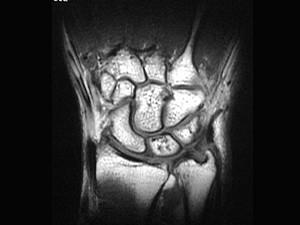

问题 男,27 岁,外伤后尺腕部疼痛,结合图像,最可能的诊断是 ( )

选项 A、尺骨骨折 B、三角纤维软骨复合体裂伤 C、三角骨无菌性坏死 D、三角骨骨折 E、未见异常

答案 B